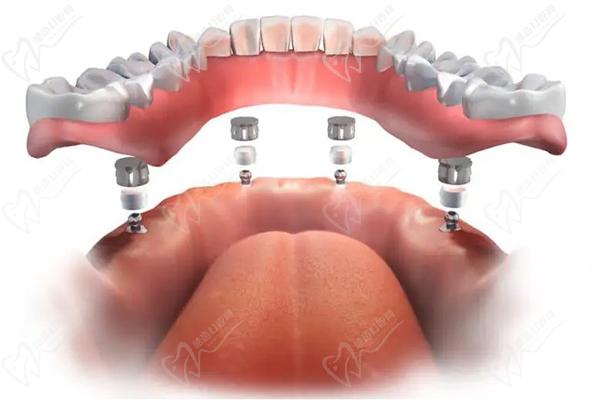

廣州曙光美云口腔醫(yī)院采用的全口即刻種植牙技術(shù),也被稱(chēng)為"ALL-ON-4"或"ALL-ON-6"種植技術(shù),是目前種植牙領(lǐng)域先 進(jìn)的技術(shù)之一。該技術(shù)可以在當(dāng)天完成全口缺牙的修復(fù),并能長(zhǎng)期使用,具有以下優(yōu)勢(shì):

廣州曙光美云口腔醫(yī)院全口即刻種植牙采用4顆或6顆種植體植入牙床,在上面安裝基臺(tái)并連接,后安裝"拱形連橋"牙冠。這種方式不會(huì)影響植體和牙槽骨的骨結(jié)合,而且能獲得與傳統(tǒng)延期種植相同的骨結(jié)合效 果。同時(shí),它還能避免增加骨粉膜重建和修復(fù)的過(guò)程,大大縮短了種植時(shí)間,減輕了患者的痛苦。簡(jiǎn)單說(shuō)就是:

縮短種植時(shí)間: 無(wú)需等待骨結(jié)合,當(dāng)天即可恢 復(fù)咬合功能。

即刻負(fù)重:種植手術(shù)完成后,即可安裝臨時(shí)義齒,恢 復(fù)咀嚼功能